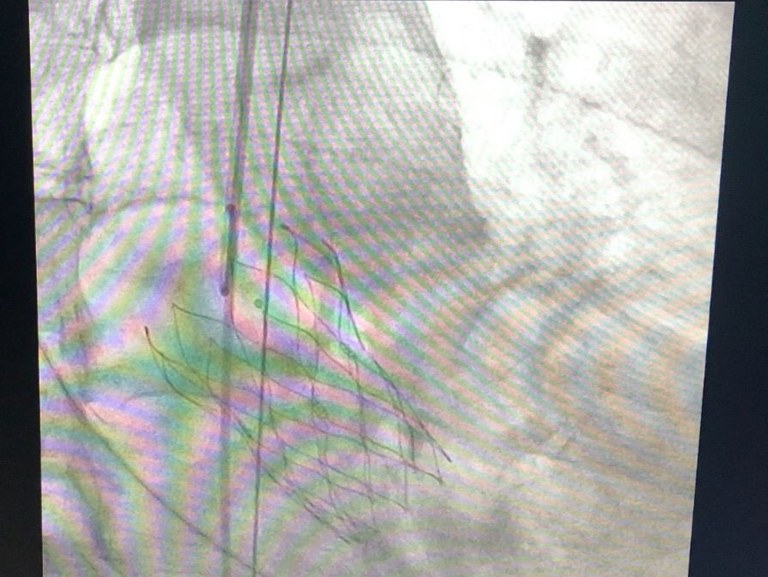

De acordo com o cirurgião cardiovascular Thiago Vila Nova, o TAVI consiste em colocar uma prótese no anel valvar aórtico, e o implante é feito por meio de uma punção na virilha, pela artéria da perna. A prótese é guiada por um cateter, através de radioscopia e ecocardiografia, até ser posicionada no anel aórtico.